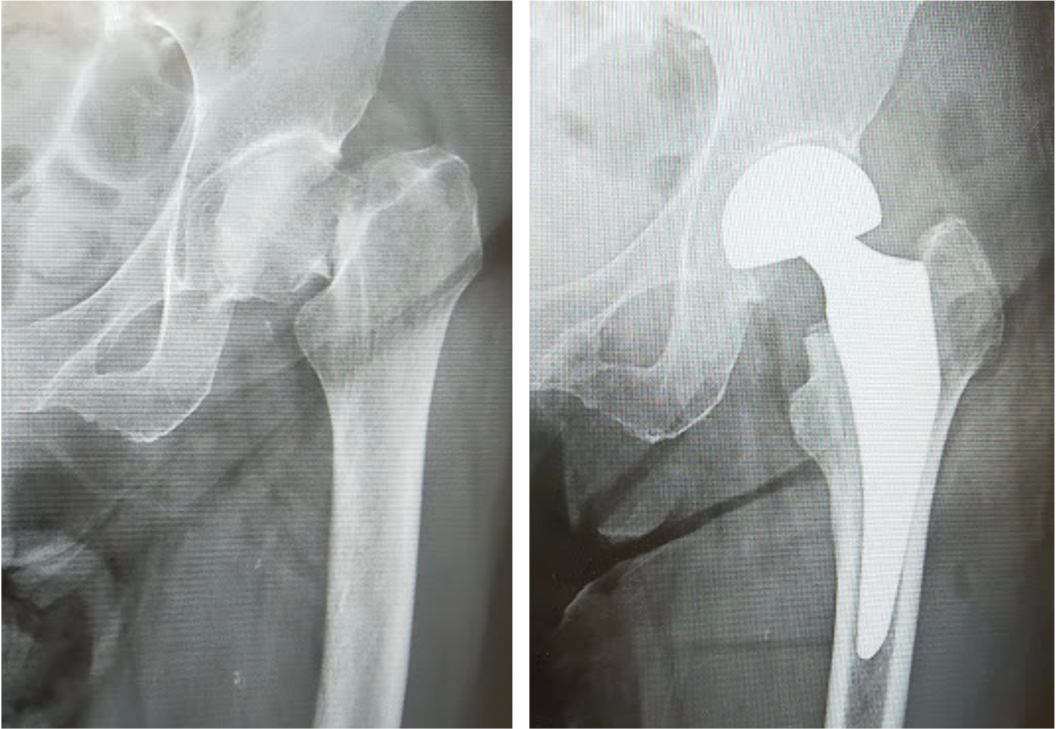

大腿骨近位部骨折は骨粗鬆症が基礎にある高齢者に非常に多い骨折です。寝たきりになりやすく、また生命予後にも関わるため、早期の手術が望ましい骨折です。

大腿骨転子部骨折に対する骨接合術

大腿骨頸部骨折に対する人工骨頭挿入術